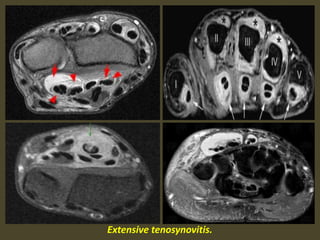

Tenosynovitis.

Tenosynovitis is an inflammation of the tendon sheath , either primary or secondary.

Marked inflammatory tenosynovitis.

Tenosynovitis of the flexor tendons.

Tenosynovitis of all flexor tendons FDS, FDP, FPL

Extensive tenosynovitis.